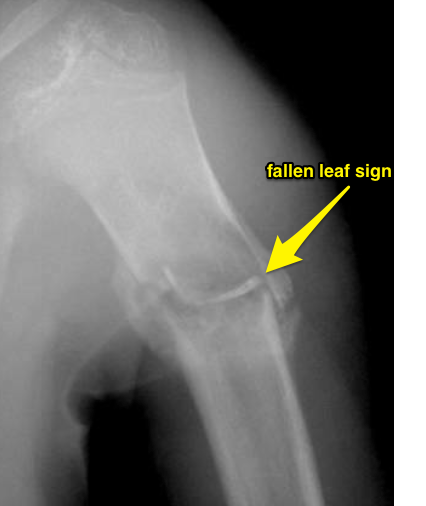

What is seen on radiographs with unicameral bone cysts?